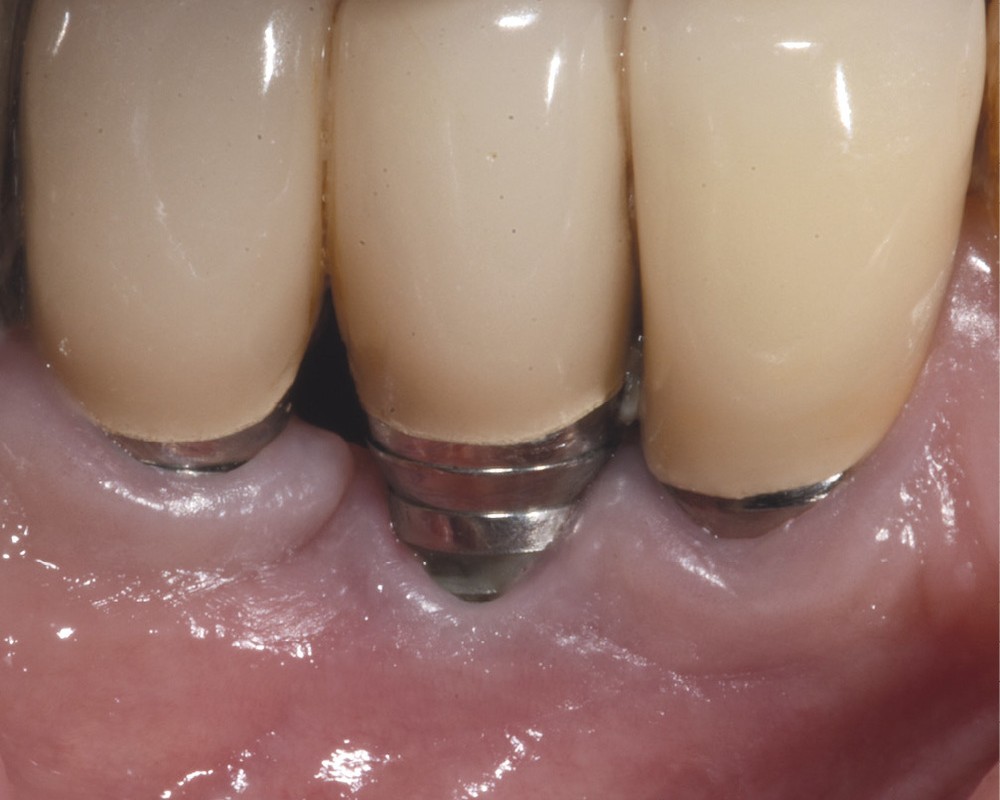

4. L’aménagement tissulaire – via l’apport d’un greffon conjonctif enfoui – a permis d’optimiser le contrôle de plaque favorisant un retour à la santé péri-implantaire (courtoisie Dr J. Malet).